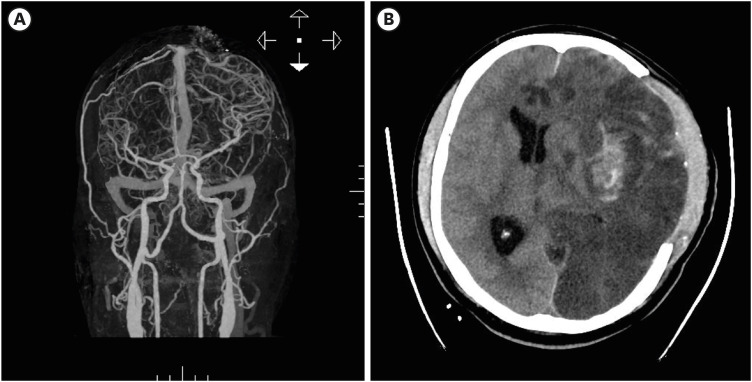

We present a unique case of a gunshot wound to the head and neck in a 51-year-old male in Korea, where such injuries are extremely rare. The case involved complex emergency procedures including neurosurgery and lingual artery ligation, complicated by worsening cerebral conditions. This report contributes to the limited Korean literature on such injuries, providing insights into their management and the importance of immediate multidisciplinary medical interventions for gunshot trauma.